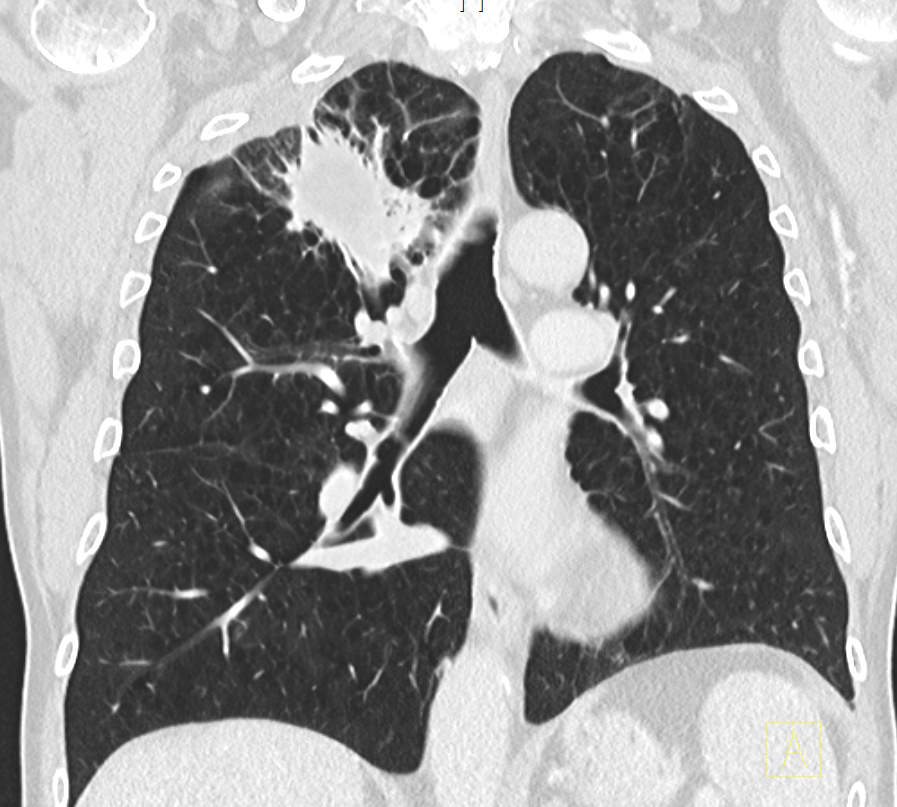

Adenokarzinom des rechten Lungenoberlappens mit Einbruch und Blutung in die Trachea.